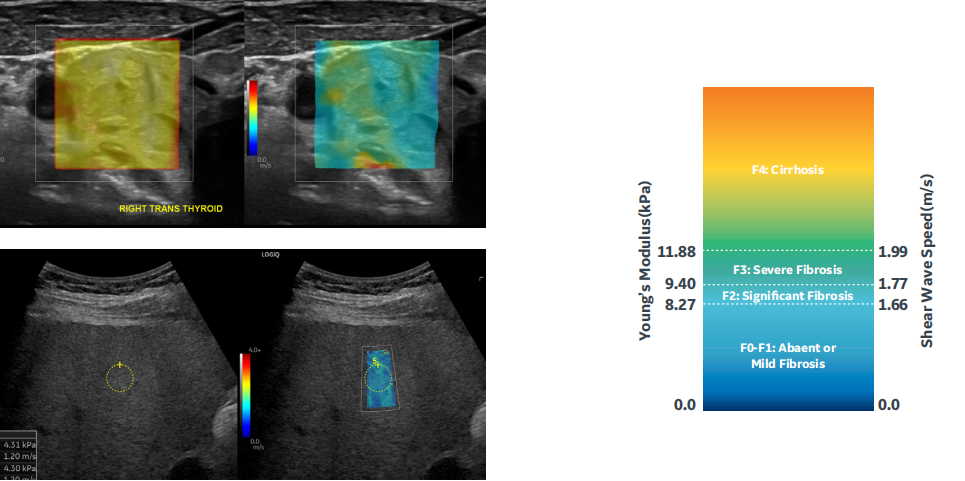

复合剪切波弹性成像:

基于cSound™平台强大、快速的处理能力,复合剪切波弹性成像具有良好的易获性和重复性,有助于得到更准确的测量值。

剪切波弹性成像技术 Shear Wave Elastography 通过一次性多组冲击脉冲提高剪切波强度,获得组织弹性模量值,并通过彩色编码方式在图像 上实时显示,反映感兴趣区域内组织各部分硬度。结果以 kPa 或 m/s 为单位,可提供最大值、 最小值、平均值、标准差、中位数、深度、面积、比值、质控参数等 12 组测量参数。测量结果 精确,高重复性,操作流程优化简洁,成像及测量速度快。